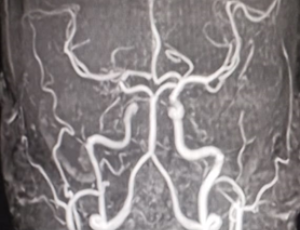

Central Nervous System (CNS) Vasculitis in a Patient with Systemic Lupus Erythematosus (SLE) and Lupus Nephritis: A Case Report

Systemic lupus erythematosus (SLE) is characterized by diverse symptoms including fever, joint pain, facial rash, blood in urine, and sores in the mouth. Neuropsychiatric SLE (NPSLE) refers to neurological and psychiatric manifestations in SLE patients after exclusion of other potential causes. A 21-year-old woman with established lupus nephritis presented with left-sided weakness, aphasia, confusion and focal neurological deficits. Imaging studies demonstrated multiple infarcts and central nervous system (CNS) vasculitis.